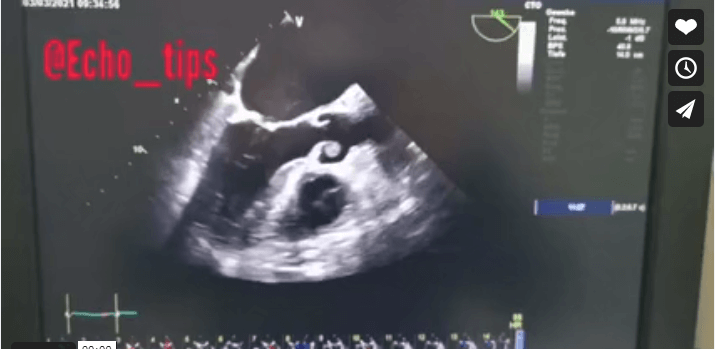

72 years ald female patient admitted to hospital because of delirium and hypertensive crises. In TTE we found clearly suspicious finding on the RCC of the Aortic Valve.

For further clarification we did TEE and it shows the above seen finding/s.

In Cardio-MRT the above seen finding was confirmed excluding artefacts

In PET CT no activities suspicious for Endocarditis or Malignancy.